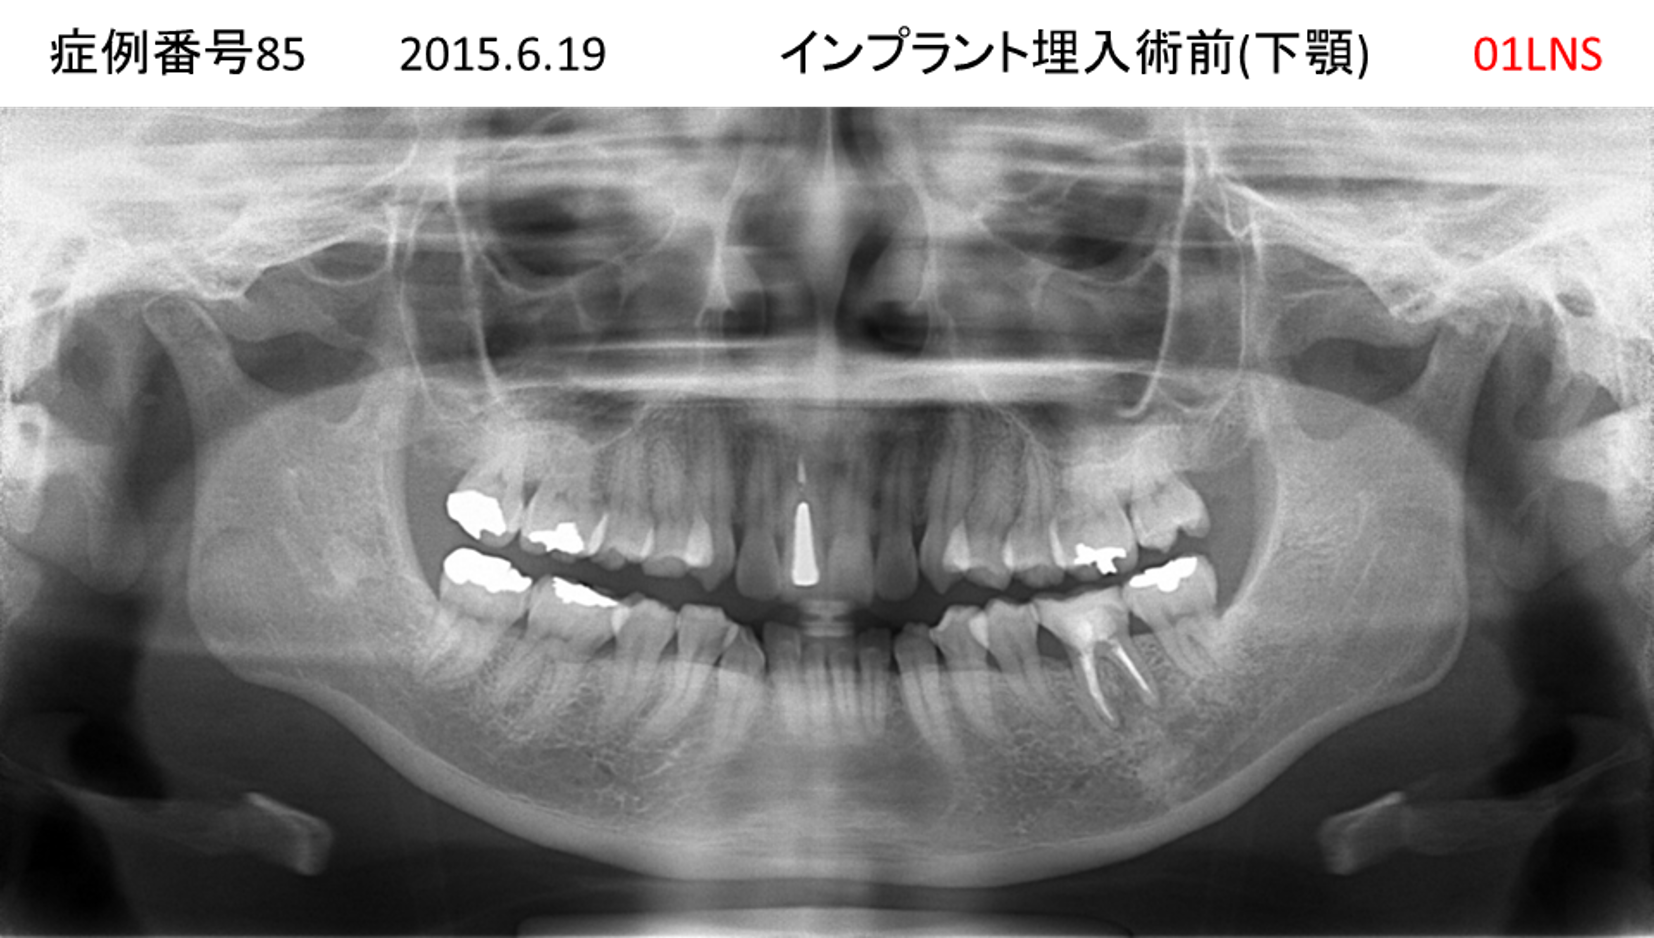

奥歯で噛めない患者様のインプラント症例

| 治療名称 |

インプラント |

| 治療費用 |

365万円+税 |

| 治療期間 |

5か月 |

| 患者さんの症状(主訴) |

奥歯で噛めない。上の前歯が揺れてきた。 |

| 治療内容 |

抜歯即時インプラント |

| 治療結果 |

食事に困らない。見た目がとても良くなった。 |

| 治療の注意点(リスク/副作用) |

インプラントが壊れたら再治療が必要 |